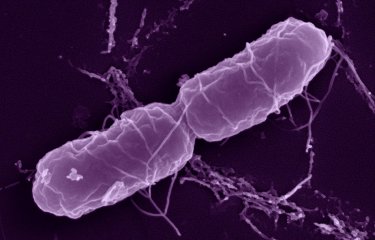

Salmonella enterica serovar Panama, one of the most common causative agents of non-typhoidal Salmonella disease in France's overseas territories, is...